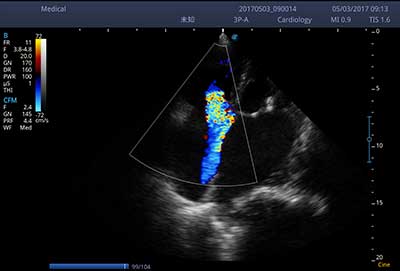

E3便携式彩色多普勒超声诊断系统拥有专业超声技术平台、高度集成化的硬件模块和结构设计、简便的操作流程、支持三探头接口全激活,兼顾了优质图像、轻便机身以及台便两用的临床使用需求。无论在常规超声科门诊检查,还是在急诊、麻醉、ICU、户外等各种应用场景。都能给您带来流程的操作体验。